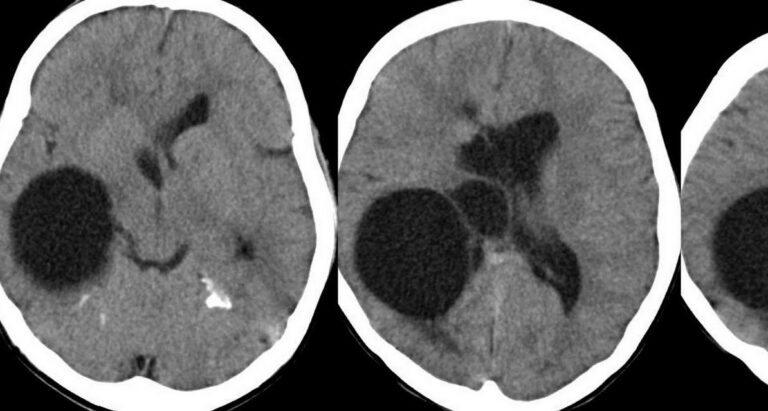

Esquizencefalia

Vídeo cortesia do Dr. Jader Cruz – The Fetal Medicine Foundation Esquizencefalia A esquizencefalia é uma malformação…